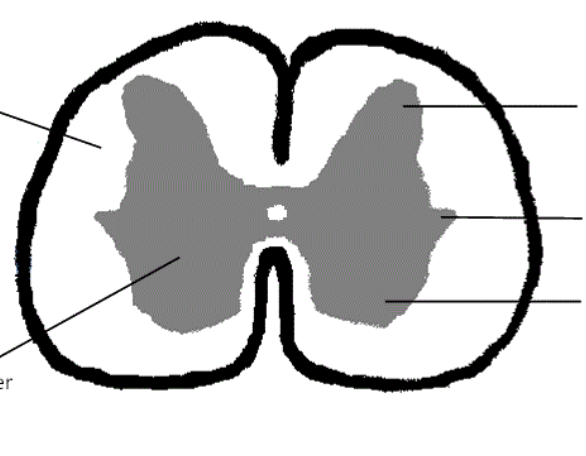

gray matter

posterior horn

anterior horn

lateral horn

gray commissure

central canal

white matter

posterior funiculus

anterior funiculus

lateral funiculus

posterior median sulcus

anterior median fissure